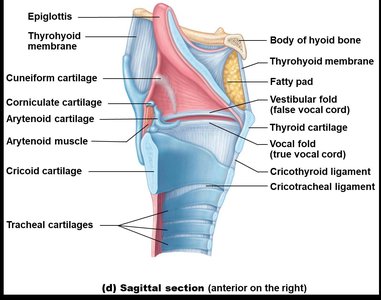

The Larynx

The larynx connects the pharynx to the trachea and is responsible for voice production, maintaining an open airway, and routing air and food using the epiglottis.

Cartilages: Includes thyroid, cricoid, arytenoid, and epiglottis.

Vocal Folds: True and false vocal cords for sound production and airway protection.